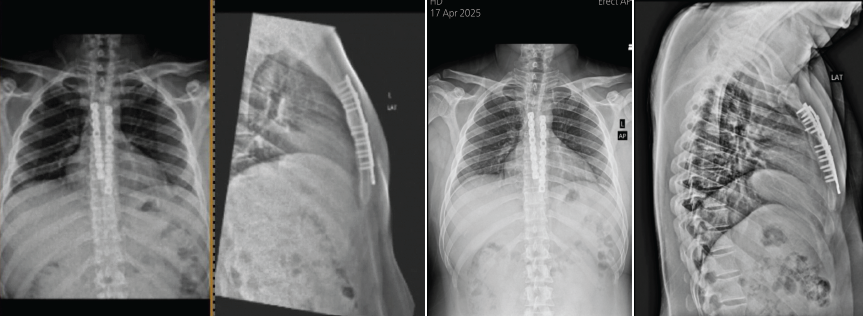

The plates were initially secured with cortical screws, followed by locking screws bicortically, while ensuring that drilling was performed cautiously and checked under thoracoscopy to avoid irritation of underlying structure (Vid). Final reduction was deemed satisfactory and confirmed through fluoroscopy and thoracoscopy. The wound was closed in layers and stapled. The post-operative period was uneventful, and the patient was able to sit upright the following day. Sutures were removed on 12th postoperative day, and follow-up X-rays (Fig. 6) showed that the implants were in good position.

Figure 6: Final check xray and 1yr follow up x ray.

The patient was advised to perform respiratory exercises and wear a rib binder for support. At 6-month follow-up, the patient relieved of chest pain and was functionally doing well.